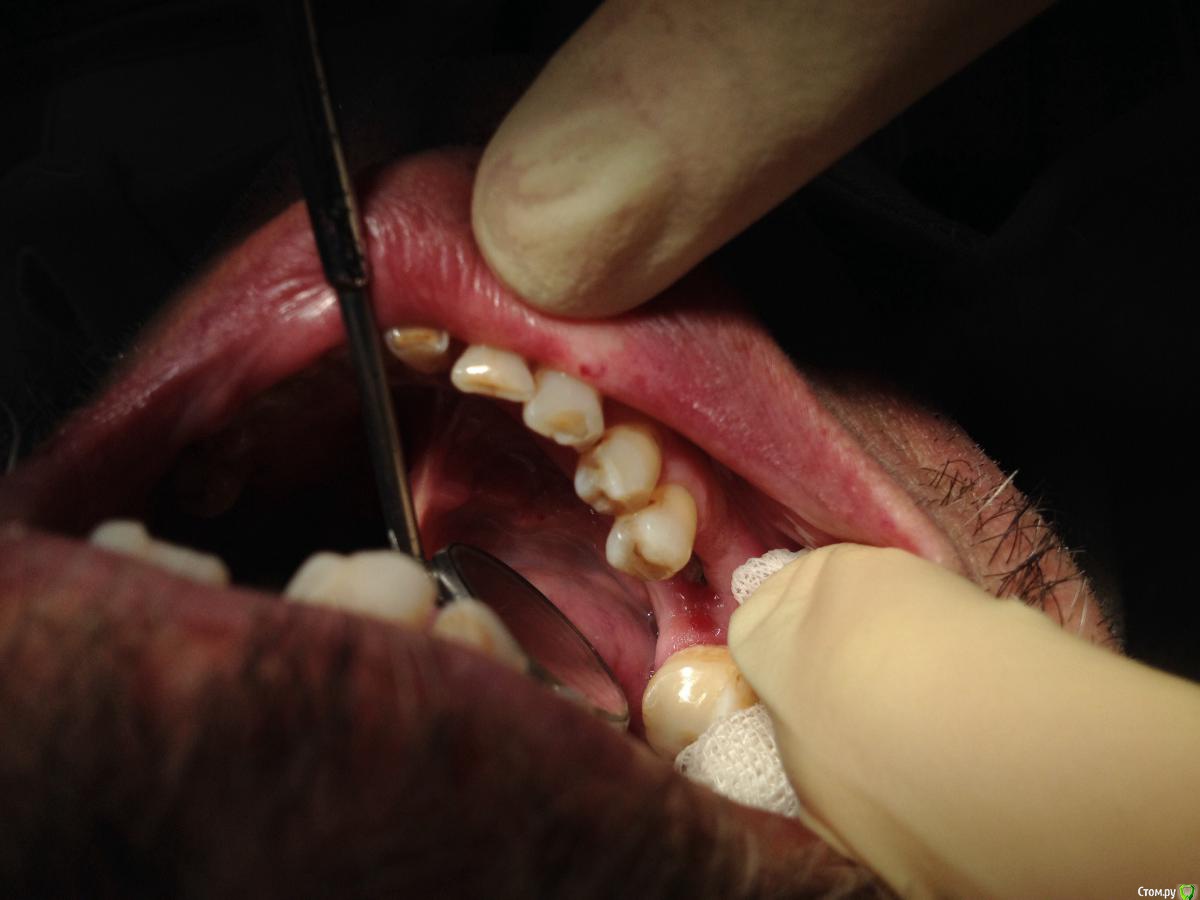

Shakirbura Опубликовано 28 января, 2016 Автор Поделиться Опубликовано 28 января, 2016 (изменено) Дождался эпителизации. Раскрыл через 3 месяца. Вроде норм все. Мой первый фдм. Всем большое спасибо!Парестезия к сожалению пока что не прошла( Изменено 28 января, 2016 пользователем Shakirbura Ссылка на комментарий

Карен Аванесов Опубликовано 31 января, 2016 Поделиться Опубликовано 31 января, 2016 Как пациент на осложнение реагирует? Ссылка на комментарий

Shakirbura Опубликовано 31 января, 2016 Автор Поделиться Опубликовано 31 января, 2016 Как пациент на осложнение реагирует?Спокойно, с пониманием. Ссылка на комментарий

Карен Аванесов Опубликовано 31 января, 2016 Поделиться Опубликовано 31 января, 2016 Тогда считайте вам повезло. 2 Ссылка на комментарий

Shakirbura Опубликовано 31 января, 2016 Автор Поделиться Опубликовано 31 января, 2016 Тогда считайте вам повезло.Так и считаю Ссылка на комментарий